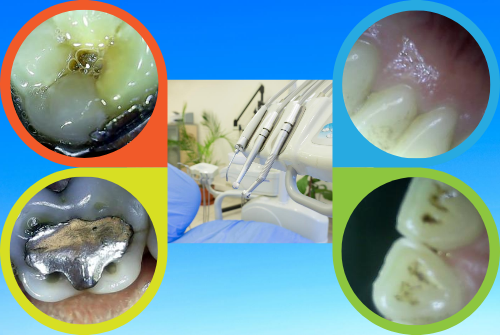

Atención cálida y personalizada;

Sanitización, desinfección, instrumental esterilizado;

Diagnósticos precisos y reales;

Observarás tu dentadura en imágenes de alta definición;

Cámaras intraorales y equipos radiológicos de última generación;